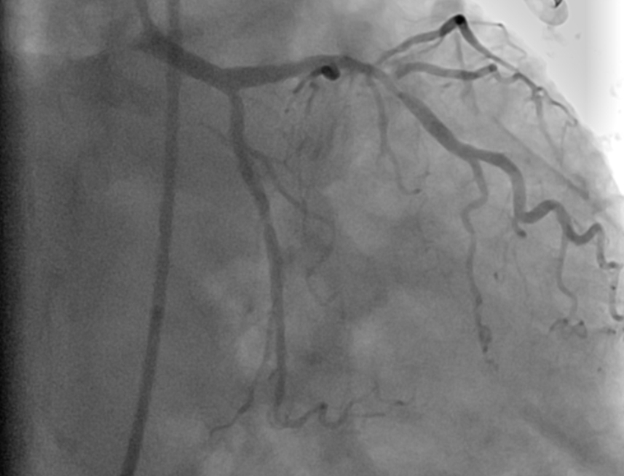

Case Summary: This case report presents the case of a 70-year-old female who presented to a community hospital in Pakistan in January 2024 with chest pain and progressive dyspnea that started seven days after an MI diagnosis. Her echocardiogram revealed an apical VSD, while coronary angiography confirmed dual-vessel coronary artery disease. Subsequently, she underwent elective subacute surgical repair of a 3x3 cm apical VSD along with coronary artery bypass grafting (CABG) and intra-aortic balloon pump placement. Postoperatively, she developed a ventricular thrombus, which was managed with anticoagulation. Follow-up echocardiography demonstrated marked clinical improvement.